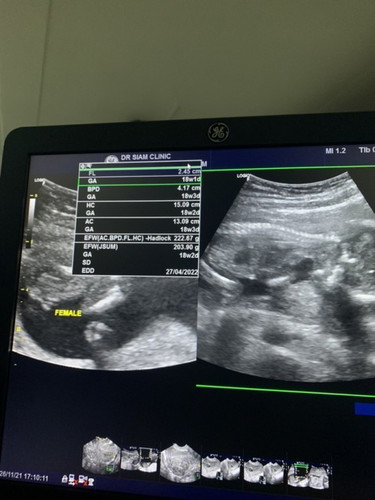

ขออนุญาตสอบถามแม่ๆนะคะ ตอนไปฝากท้อง18wที่คลีนิคหมอซาวด์ท้องให้ดูว่าได้ผู้หญิง หมอบอกค่อนข้างชัด พอ27wเปลื่ยนไปฝาก รพ หมอบอกไม่เห็นเพศเลย ตอนนี้เข้า38wหมอก็ไม่ได้ซาวด์ให้อีกเลย โอกาสที่ได้ผู้หญิงจะดูได้ยังไงค่ะ หรือต้องรอคลอดเลยค่ะ แต่เตรียมของ ของเด็กผู้หญิงหมดเลย🥺#คุณแม่ๆช่วยแนะนำหน่อยค่ะ